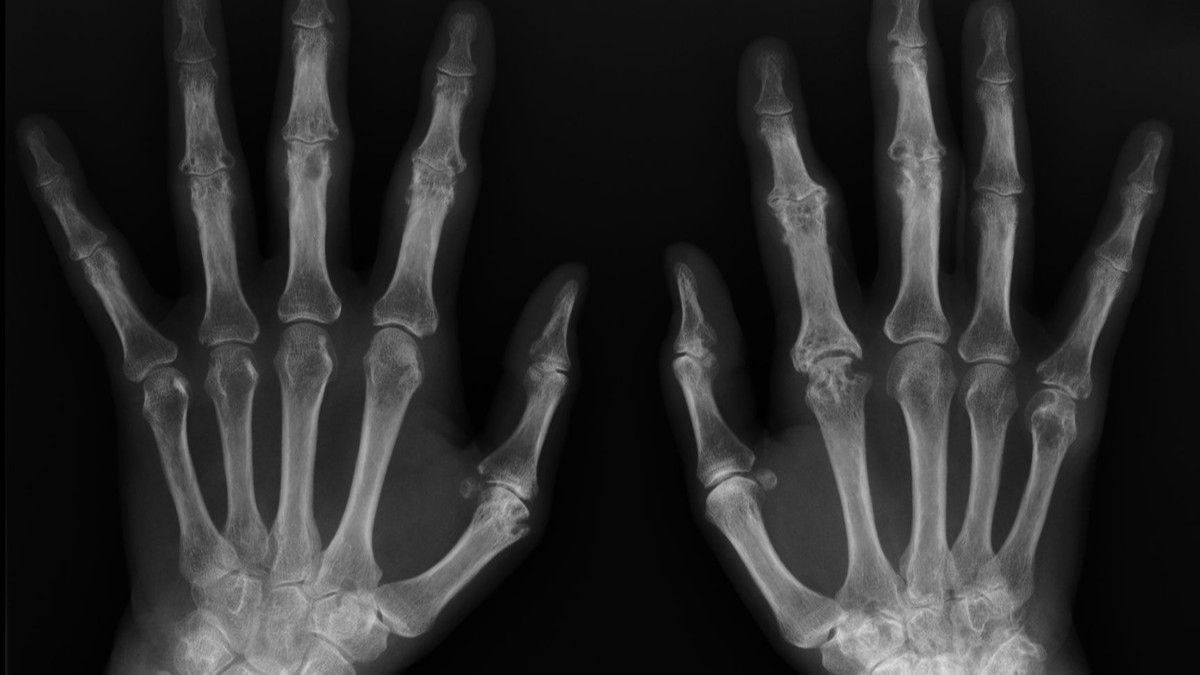

Kemik yaşı tespiti el – bilek röntgen filmlerinin radyolojik incelenmesi ile gerçekleştirilir. Bu amaçla kullanılan Greulich – Pyle Atlası kronolojik yaş gruplarına göre olması gereken standart el – bilek kemik haritalarından oluşmaktadır.

Bu yöntemde el –bilek röntgen filmi atlastaki şablonlarla karşılaştırılarak kemik yaşı tespit edilir.